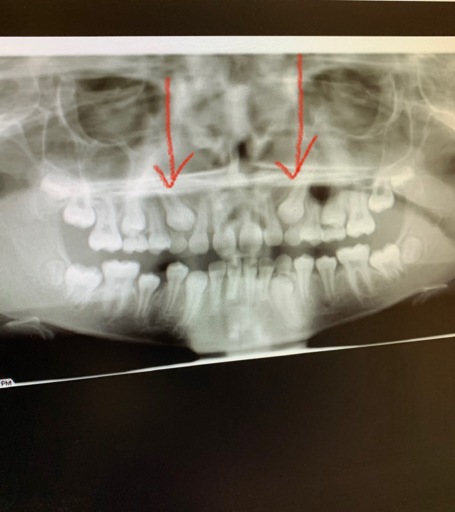

Teeth bent and twisted and a lot of pain given

For a long time I have been expriencing a lot of pain I'm my teeth when I eat drink and not do anything with them, when I eat I go through a lot of pain and feel sick and light headed because of it. My teeth are twisted and bent and one of them which is my adult tooth and another one which is my adult tooth feels like it's going to fall out which gives me more pain as they have been pushed backwards and forwards and I'm looking on some advice to do.